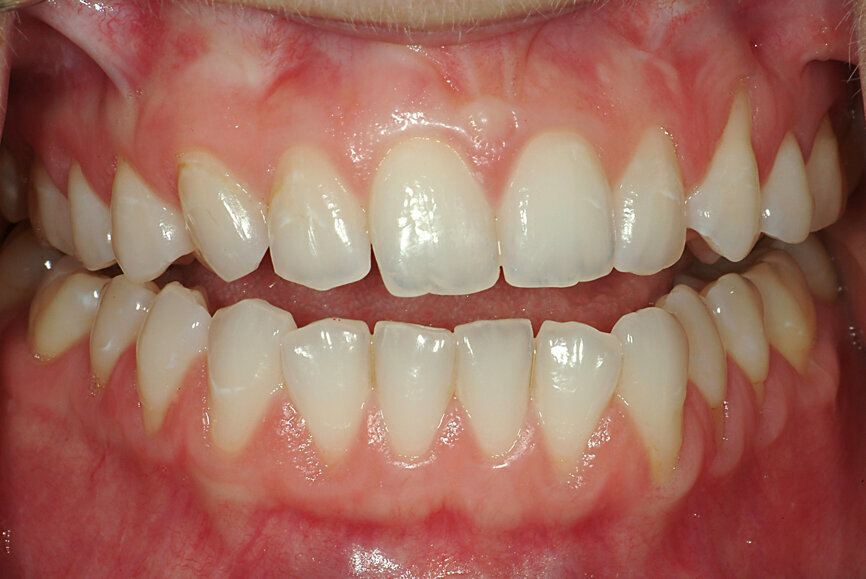

Fig. 20a: Digital recording of intercuspation.

Fig. 20b: Digital recording of intercuspation.

When the dentist decides to maintain the existing bite, that is, to work with what is there, the focus should be on ensuring that there is no unwanted change in the recording and transmission to the laboratory. Analogue recordings of existing IC can be performed using polyvinylsiloxane registration pastes or waxes (Fig. 19). Dental laboratories usually digitise the analogue records and fabricate the restorations digitally. The process of digitisation can introduce imprecisions, owing to the difficulty of the laboratory articulating the models in the precise position. Digital recordings of existing IC can be performed using intra-oral scanners. The scanner is placed in the buccal corridor and records the relative position of the maxillary and mandibular teeth (Figs. 20a & b).